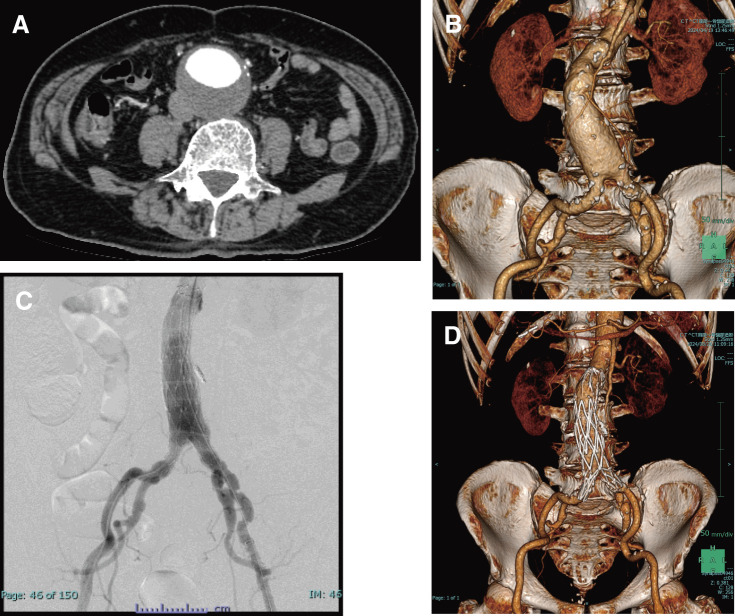

Cold agglutinin disease (CAD) is a rare and autoimmune hemolytic disorder caused by the presence of cold-reacting autoantibodies against red blood cells. An abdominal aortic aneurysm (AAA) is a potentially life-threatening condition. This report describes an 83-year-old man with AAA who was diagnosed with primary CAD 9 years before undergoing AAA surgery. The patient underwent successful endovascular aortic repair. Temporary hemolytic anemia and exacerbation of jaundice were observed postoperatively despite strict temperature control. Red blood cell and haptoglobin transfusions may prevent fatal hemolytic anemia, renal disorders, embolism, and systemic complications.